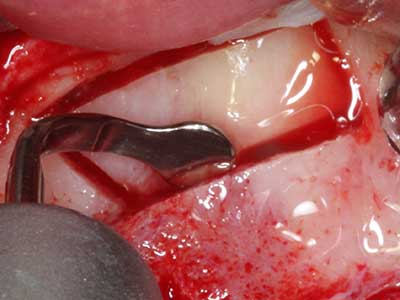

Фиг. 3: Базалното разделяне на блока е по-лесно със специалните извити накрайници.

Фиг. 13: Подходяща иригация с остатъчна 4 mm дебелина на костта е важна за този 52-годишен пациент по време на разделянето на костта.